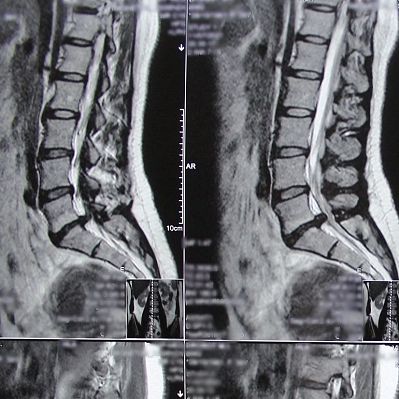

«Обычно к грыже межпозвоночного диска приводят малоподвижный образ жизни, большая масса тела, большая не физиологичная нагрузка на позвоночник, наследственность (врожденная слабость соединительных тканей), старение диска (он теряет влагу, перестает выполнять функцию амортизатора и выпадает в просвет позвоночного канала), - рассказывает врач-нейрохирург Нина Николаевна Вознесенская @voznesenskai_neirohirurg - У нашей пациентки фактор лишнего веса полностью отсутствует, а вот другие моменты есть».

Пациентке провели эндоскопическое удаление грыжи диска (эндоскопическая микродискэктомия) - в отделении максимально используют миниинвазивные (малотравматичные) методики. В частности, эндоскопическая микродискэктомия - удаление грыжи с помощью эндоскопа диаметром 4 мм, специальных миниатюрных инструментов-манипуляторов под визуальным контролем на экране видеодисплея. Операция проводится через миниатюрный прокол мягких тканей. Это сокращает риск осложнений и существенно уменьшает послеоперационный реабилитационный период. Выполняется операция под общим наркозом или спинальной анестезией.